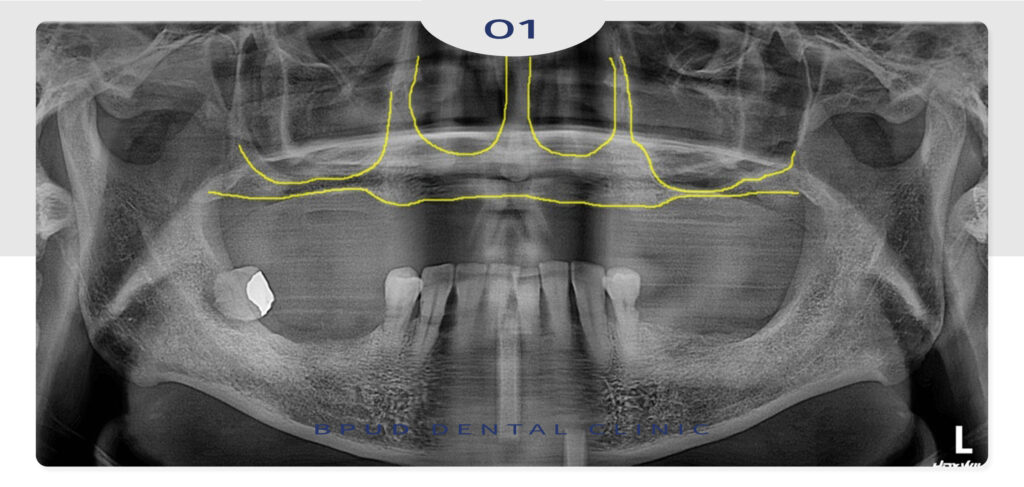

타 치과에 내원하였을 때는

상악동이 너무 가깝고 앞니 치조골이

너무 흡수되어 임플란트가 어렵겠다는 말씀을

듣고 오셨다고 합니다.

전체 골격성 3급 부정교합이 있으셨고

상악의 치조골이 과도하게 흡수되어

일반 보철 진행 시 너무 앞으로 튀어나올 수 있는

상황에서 양쪽 상악동 거상술 및 앞니 골이식술을